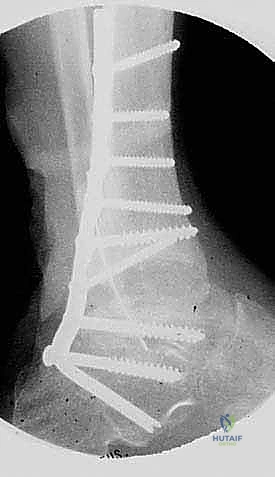

FIG 8 • Weight-bearing lateral radiograph 3 months postoperatively.